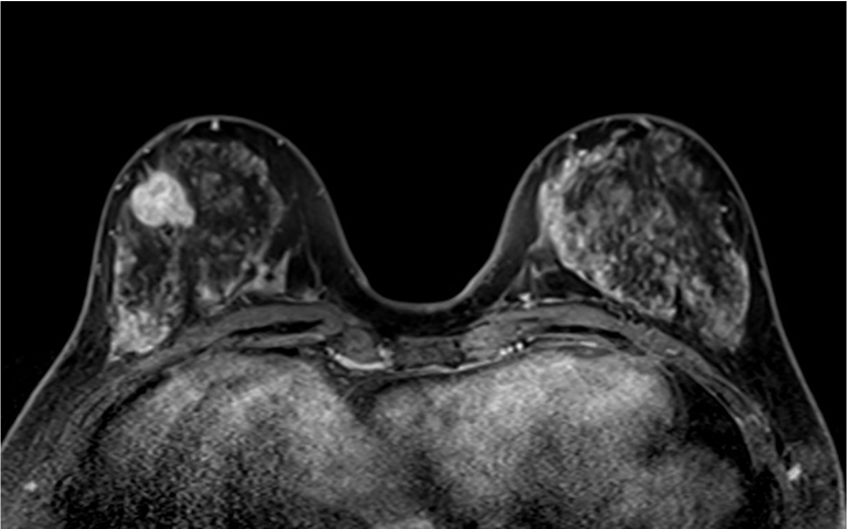

4. ダイナミックMRI (造影前 早期相 遅延相)

早期相で、乳腺の辺縁にBPE(矢印)を認めるが、その範囲は広くなくmildと判定する。乳癌の病変は、早期相から急速に造影され、遅延相でwash outがみられる。BPEは、遅延相で拡大し増強している。